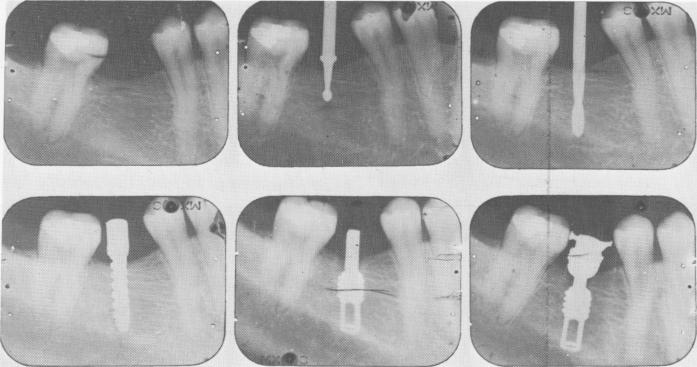

Fig. 8-8. Intraoral radiographs illustrating the step-by-step technique. (From Linkow, L. I.: The age of endosseous implants, Dent. Concepts, Spring, 1966.)

As is important in all implant interventions, radiographs were taken before, during, and after implant insertion (Fig. 8-8).

1 Radiographs showing step-by-step endosseous implantation technique